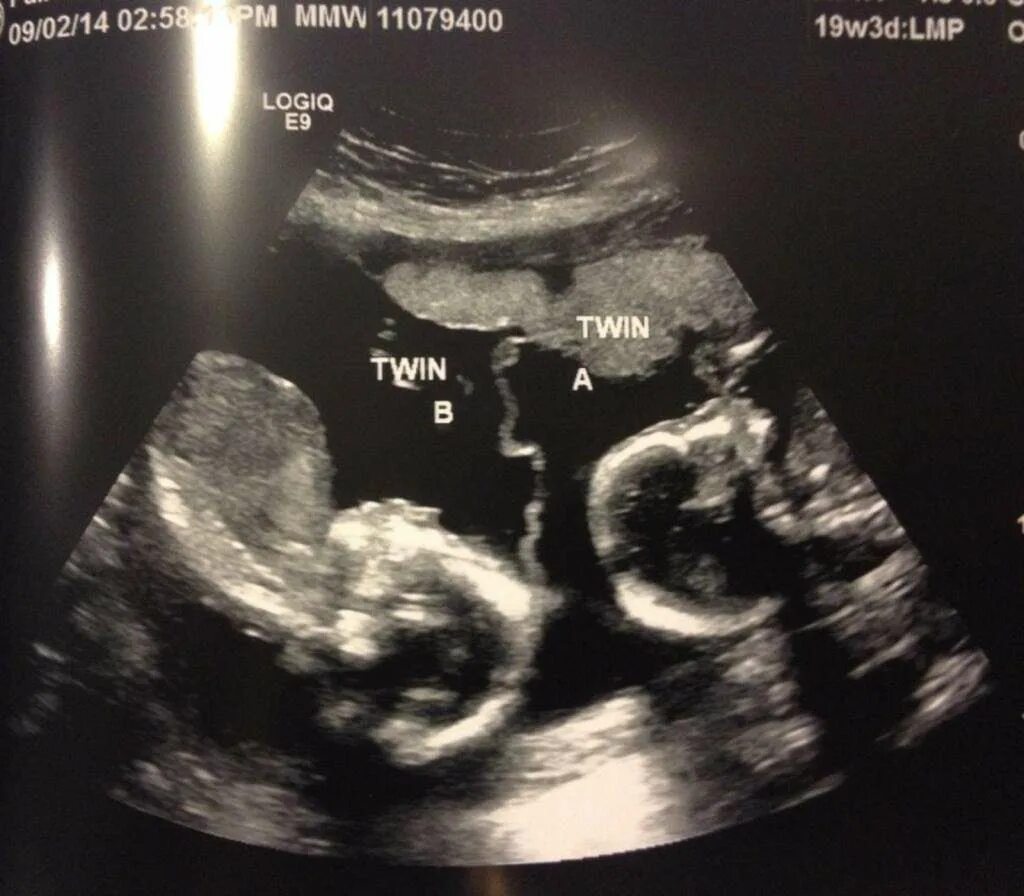

14 неделя ощущение